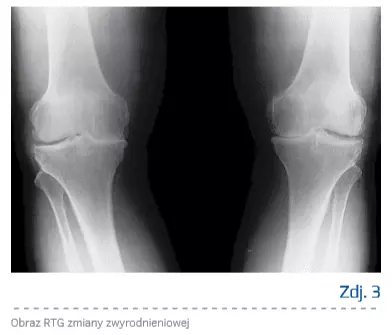

Choroba zwyrodnieniowa

Choroba zwyrodnieniowa stawów dotyka coraz większą część społeczeństwa. Wydłużający się czas życia i mała ilość ruchu stwarzają sprzyjające okoliczności dla rozwoju choroby. Chrząstka stawowa stanowiąca wieńczącą kość strukturę narażona jest na nacisk, wstrząsy oraz ciągły ruch ślizgowy trących o siebie powierzchni stawowych. Zaburzenia w jej prawidłowej strukturze doprowadzają do rozwoju zmian zwyrodnieniowych. Strukturę tę stanowią chondrocyty oraz macierz, w której są zawieszone (90% masy). Składnikami budulcowymi macierzy są głównie woda (powyżej 65%), białka i lipidy, a spośród białek należy wymienić przede wszystkim kolagen oraz proteoglikany.

Proces zapalny powoduje destrukcję chrząstki stawowej i prowadzi do utraty stabilności chrząstki, jej przebudowy i włóknienia. W dalszym etapie dochodzi do sklerotyzacji kości w okolicy podchrzęstnej. Istotą zmian zwyrodnieniowych jest to, że proces nie toczy się tylko w obrębie chrząstki stawowej, ale obejmuje cały staw (podchrzęstna warstwa kości, błona maziowa, torebka stawowa itd.).

W przypadku reumatoidalnego zapalenia stawów uzyskano ewidentne efekty zmniejszenia procesu zapalnego, jednak wobec wątpliwości, co do etiologii choroby zwyrodnieniowej stawów – czy proces zapalny występuje pierwotnie, czy też wtórnie – stosowanie preparatów niezdenaturowanego kolagenu typu II pozostawało przedmiotem dyskusji. W badaniach stwierdzono, że w przebiegu choroby zwyrodnieniowej przez błonę maziową są produkowane cytokiny, czynniki wzrostowe i prostaglandyny, co doprowadza do produkcji metaloproteinaz w komórkach macierzy chrząstki, co w dalszej kolejności skutkuje stopniową degradacją chrząstki w mechanizmie zapalnym [8]. Produkcja kolagenazy przez zmienioną zapalnie błonę maziową i aktywowane chondrocyty ma charakter samonapędzającego się mechanizmu wzmagającego autodegradację chrząstki i rozwoju choroby zwyrodnieniowej [9–11]. Wobec powyższego oprócz mechanizmu biomechanicznego, osteoporotycznego i metabolicznego należy wskazać także mechanizm zapalny i w zależności od etiologii stosować różną terapię – w przypadku pacjentów z zaburzeniami mechanicznymi należy pamiętać o leczeniu odciążającym, zmieniającym mechanikę stawu (redukcja masy ciała, odciążanie, wiskosuplementacja, leczenie operacyjne), w przypadku pacjentów ze schorzeniem o podłożu osteoporotycznym odpowiednia będzie farmakoterapia.